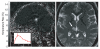

Focused ultrasound surgery (FUS) is a noninvasive image-guided therapy and an alternative to surgical interventions. It presents an opportunity to revolutionize cancer therapy and to affect or change drug delivery of therapeutic agents in new focally targeted ways. In this article the background, principles, technical devices, and clinical cancer applications of image-guided FUS are reviewed.